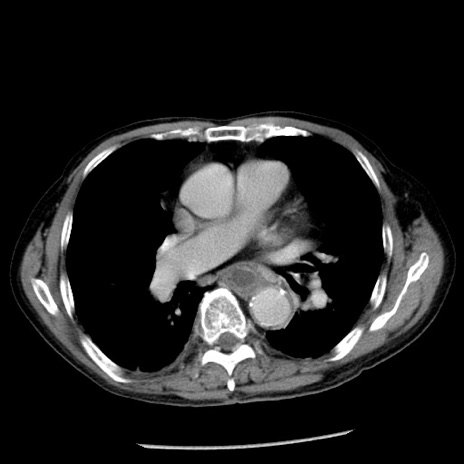

症例26(横断像)

【症例】80歳代男性

【主訴】嘔吐

【現病歴】昨晩2回嘔吐あり、今朝になっても嘔吐あり。来院。

【既往歴】胃潰瘍

【身体所見】意識清明、BT 37.6℃、BP 166/95mmHg、HR 100bpm、SpO2 97%、腹部:平坦・軟、腸蠕動音聴取良好、圧痛なし。

【データ】WBC 21900、CRP 1.46